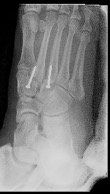

Surgery for midfoot arthritis ranges from simple to more complex procedures. Surgery may involve a “clean-up” of the joint by removing damaged cartilage and bone spurs, resection of a part of the joint, fusion (stiffening) of one or more joints. Medical imaging, such as x-rays and MRIs are usually obtained prior to surgery to determine the extent of the injury and to plan for the proposed surgery.

Rehabilitation varies according to the procedure performed. In some cases patients are allowed to weight bear immediately following surgery, but in other cases they are required to be non-weight bearing for a period of time.